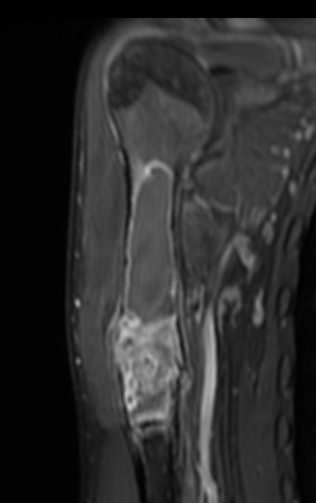

MRI

Gruenewald et al Br J Radiol 2023

- 36 patients with UBC or ABC

- fluid fluid levels / septation seen in both

- arterial feeders on MRA helped differentiate some ABC's